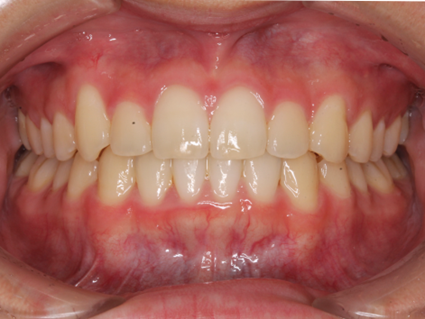

抜歯を避ける矯正処置「ディスキング」

ディスキングとは矯正治療の一環として行われる処置です。通常、歯が並ぶスペースが足りないケースでは抜歯が行われることがあります。

抜歯をすればスペースは確保できるものの、健康な自分の歯がなくなってしまうということです。それを避けるために、当院ではディスキングという選択を取ることがあります。

歯の表面には、厚さ2~3mmのエナメル質と呼ばれる硬い層が覆っています。このディスキング処置では、各歯の側面から最大0.5mmまでエナメル質を削り取ることで、歯の並びを改善するためのスペースを作り出します。例えば、前歯6本にディスキングを行うと、合計で3mmのスペースを確保できる計算になります。さらに、前歯以外の歯にもディスキングを施すことで、最大5mmほどのスペースを作り出すことが可能です。

ディスキングは、削るというよりもヤスリで歯を磨くような繊細な処置で行われます。そのため、通常は痛みやしみるような不快症状が生じることは少なく、比較的負担の少ない治療方法です。